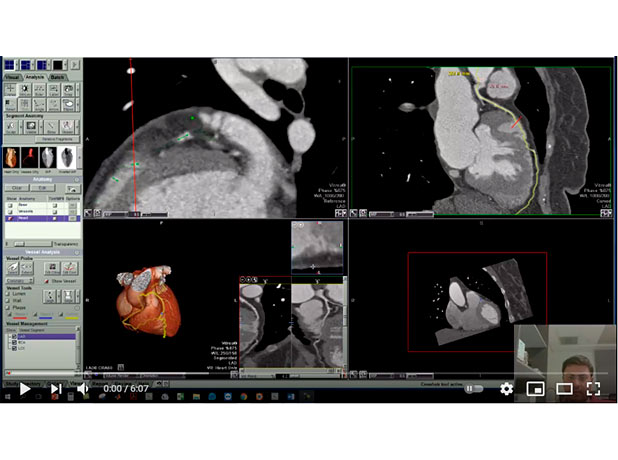

Cardiac CT full Anatomy

Mohamed Gibreel , FEBR (Fellowship of Egyptian Board of Radiology ) Cardiac imaging consultant at Aswan heart center -Magdi Yacoub Foundation , Egypt